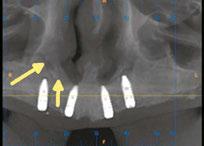

on the crest of the ridge in the region of teeth Nos. 15-25. While creating the incision, bleeding was noticed in the region of tooth No. 15 which intensified during the flap reflection (Figure 2). Bleeding was pulsatile, indicating an arterial bleed. Initially attempts to control bleeding included a pressure pack and ice pack, and the bleeder was isolated, and the vessel ligated (Figure 3). The bleeding could be controlled, and the procedure was completed by placing four Bioner implants (Bioner, Spain), size 4/10 mm. Sutures were placed, and patient was kept on basic medication for pain and infection control. Immediately after the surgery, the patient was advised to get a CBCT. As shown in Figure 4, a coronal view and Figure 4B (yellow arrows), the position of the artery can be seen.

Figure 1: Pre-op panoramic radiograph Figure 2 (left): Alveolar antral artery (AAA). Figure 3 (center): The artery has been ligated with suture. Figures 4A and 4B (right): CBCT post-implant placement and position of the artery coronally (top). 4B. Showing the position of alveolar antral artery (AAA) in relation to implant placement as indicated by the yellow arrows (bottom)